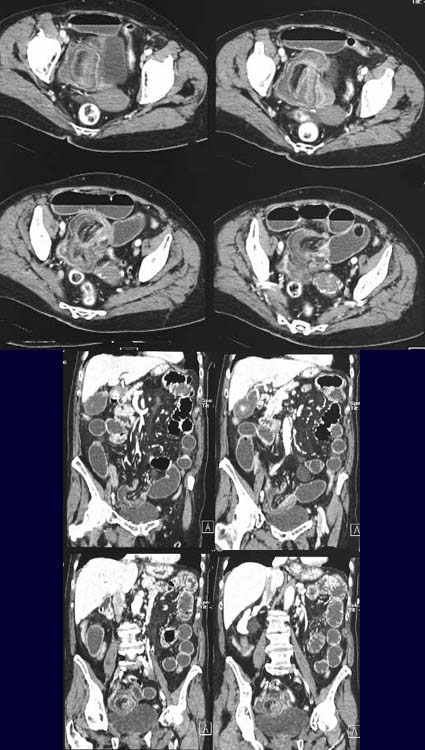

Sowohl

in der axialen Schnittführung als auch in den coronaren MPRs (multiplanare

Rekonstruktionen) lässt sich eine schießscheibenförmige

Raumforderung (Kokade) im Sinne ineinander gestülpter wandverdickter

(Ödem) Darmschlingen mit zentralem

mesenterialem Fettgewebe erkennen. Zusätzlich Spiegelbildung

im Dünndarm.